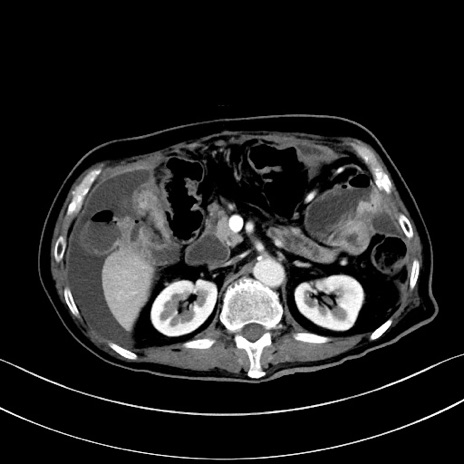

症例28(横断像)

【症例】60歳代男性

【主訴】嘔吐

【現病歴】胃癌にて胃全摘後。食思不振が悪化し、夜中に嘔吐することがある。

【既往歴】胃癌、胃全摘、脾摘、胆摘後

【データ】WBC 5900、CRP 10.56